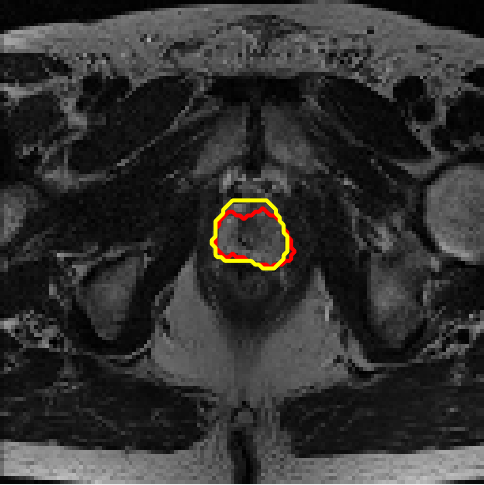

4.4 Results on PROMISE12

We assess different semi-supervised methods on the PROMISE12 dataset (Litjens et al., 2014). The PROMISE12 dataset contains 50 transverse T2-weighted MR images with the most anatomical detail. 35 and 15 cases are randomly selected for training and validation. The images were resized to 128×128128\times 128. The training dataset includes nn fully annotated images, with pixel-wise labels unavailable for the remaining 35n35-n. Table 3 presents the results. Fig. 7 offers a visual comparison of the segmentation results for different models and shows that the proposed method achieves more precise segmentation.

Figure 7: Example segmentation obtained by different methods on the PROMISE12 dataset. Red lines indicate predicted results, and yellow lines indicate ground truths.